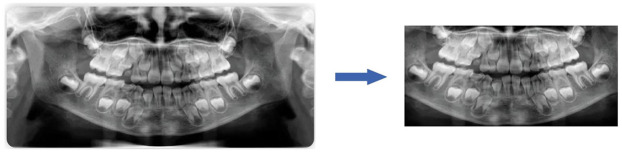

Methods: This study constructed a largescale panoramic dental image dataset and applied various convolutional neural network (CNN) models for automated age estimation.

Abstract Image